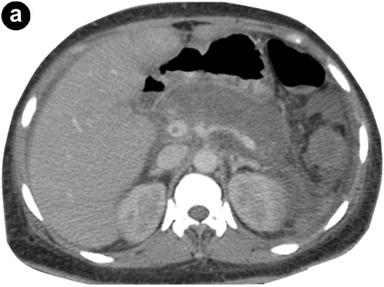

At the GI clinic 11 days post-discharge, the patient appeared toxic, weak, and complained of mild, diffuse abdominal pain and dizziness. She was found to be hypotensive (blood pressure: 85/45 mmHg and tachycardic (heart rate: 134 beats/min). On day 2 after her readmission, she spiked a fever of 102.8°F (39.3°C) and had several episodes of non-bilious vomiting. Upright abdominal radiograph showed no free air or bowel obstruction. Her serum lipase increased from 99 U/L to 427 U/L (reference range: 8-78 U/L) within 48 hours (Figure 2), while her serum amylase was only elevated on day 2 of readmission (240 U/L; reference range: 40-130 U/L). Abdominal ultrasound (US) was negative for biliary duct disease. CT scan of the abdomen revealed enlarged and nonenhancing body and tail of the pancreas consistent with pancreatic necrosis (Figure 3). Cerebrospinal fluid analysis was positive for active shedding of CMV virus (12,811 copies/mL) without signs of meningitis. The patient’s serum anti-CMV IgG antibodies were elevated (118.8 EU/mL; reference range: 0-8 EU/mL), while anti-CMV IgM antibodies were negative. No other virus was detected in the blood or cerebrospinal fluid.

Figure 3. Coronal (a.) and sagittal (b.) CT scan of the abdomen showing enlarged and non-enhancing body and tail of the pancreas consistent with pancreatic necrosis. |